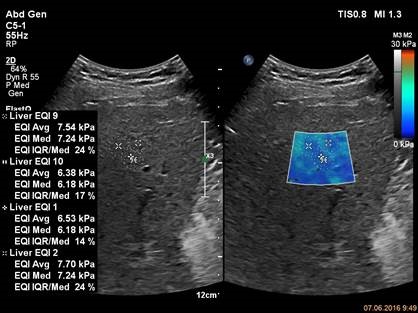

Для исследования используется прибор EPIQ 7, датчик С5-1, приложение ElastQ Три измерения показывают повышенную жесткость печени.

Для исследования используется прибор EPIQ 7, датчик С5-1, приложение ElastQ Проведенные измерения показывают высокую степень жесткости, характерную для цирроза ее ткани.